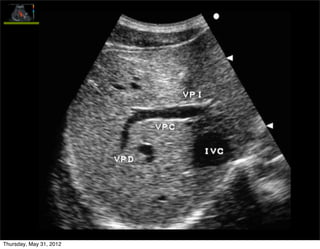

Porta principal

• Unión de esplénica y

mesentérica sup

• Orden (post a ant)

•     Porta-Colédoco-Arteria

• Diámetro 11 +/- 2 mm

• Visibles por colágena

incich/grupo ct scanner                      Departamento de Radiología/Unidad PET-CT